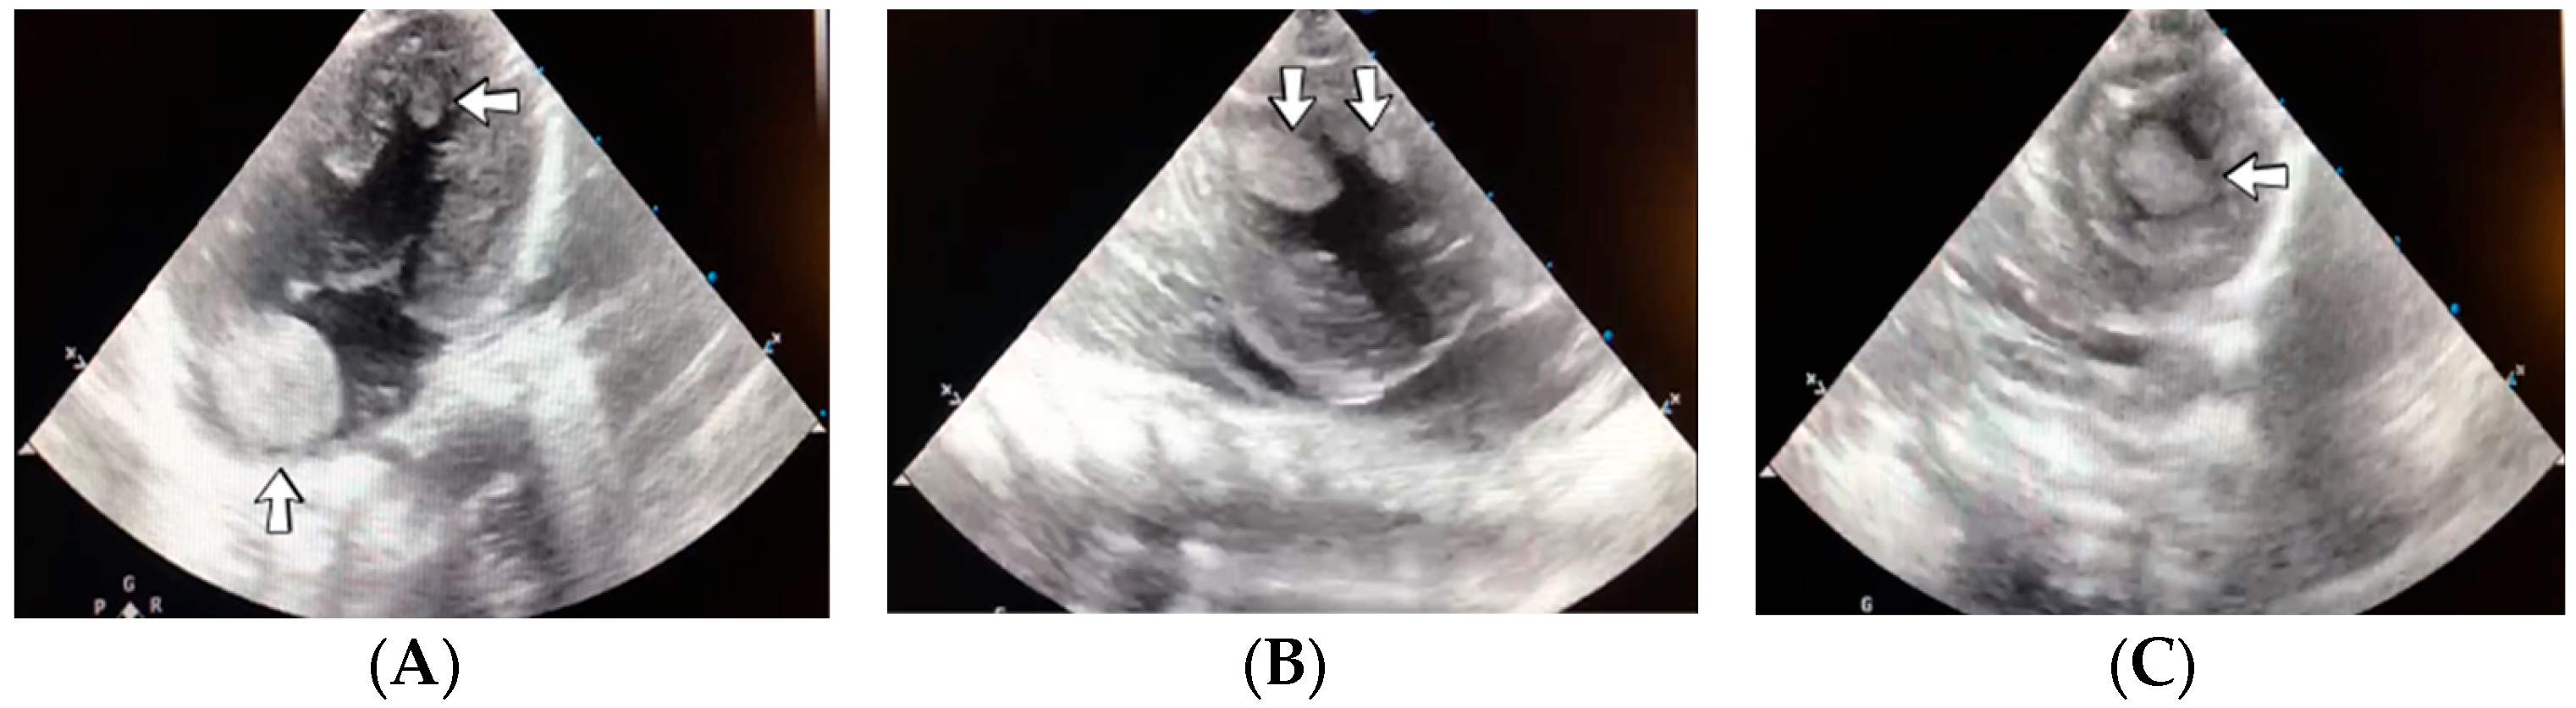

A 19-day-old male neonate (35–36 weeks, 2.20 kg) presented with thrombosis of the right pulmonary artery diagnosed on the same day at another pediatric emergency department, where treatment with continuous heparin infusion was initiated. The admission laboratory findings showed elevated c-reactive protein, modified coagulation tests (ongoing anticoagulation treatment), and elevated D-dimer tests. The cardiac ultrasound identified thrombi in the right atrium and ventricle (Figure 15). Therapy with heparin was continued, to which alteplase was added. After four days of anticoagulation and fibrinolytic therapy, the thrombi could no longer be noticed on ultrasound or CT scan.

Figure 15.

Intracardiac thrombosis was identified on cardiac ultrasound: in the right pulmonary artery (A), the right atrium (B), and the right ventricle (C).

Genetic testing confirmed inherited thrombophilia, with a positive MTHFR C677T homozygous gene mutation and Antithrombin, Protein S, and Protein C deficiencies. A mild elevation of PAI-1 levels was detected. There was limited information about the family history.